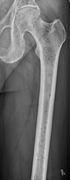

Femur with multiple myeloma lesions.